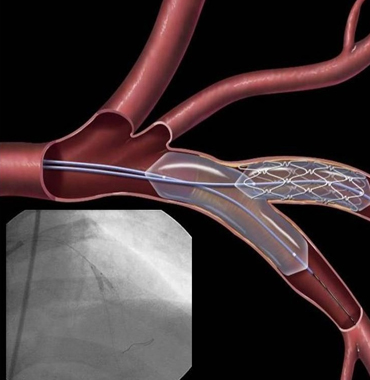

Together with a team of trained staff, his goal is to provide top care so that patients can achieve and maintain a healthy heart. He has done hundreds of angiographies and angioplasties...